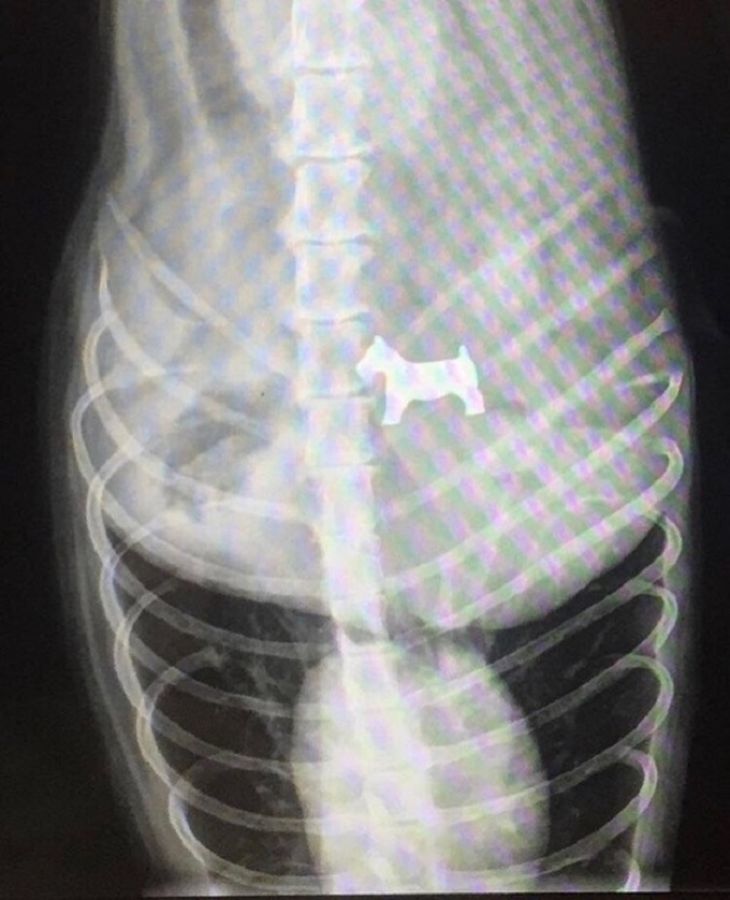

Hračkársky psík

Alfie nezniesol v dome žiadnu konkurenciu. Preto prehltol hračku psíka, ktorá bola pôvodne súčasťou hračkárskeho domčeka jeho ľudskej sestričky. Po operácií sa Alfie opäť cíti v poriadku.

(Zdroj: Manchester Evening News)